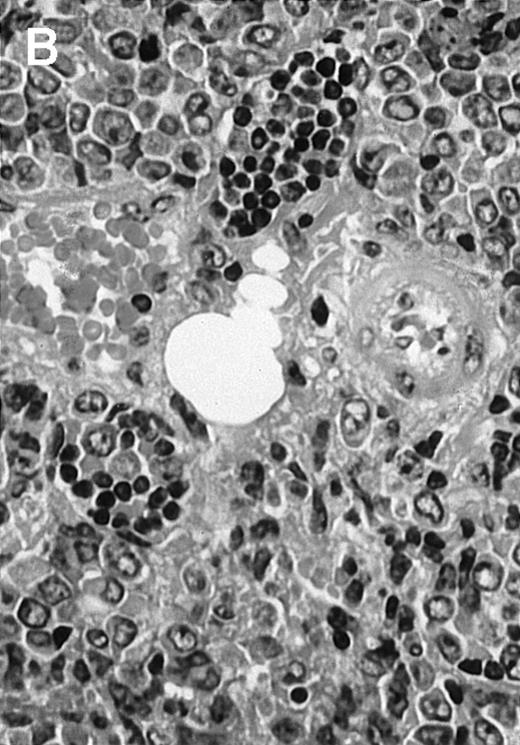

To analyze expression of the human CD40L protein in murine tissues, samples from the small intestine, colon, liver, and spleen were analyzed by HE staining as well as immunohistochemistry. We found that in mice immunized with ST40L, the Peyer's patches were prominent (Figure 1A), and the majority of cells in the Peyer's patches could be seen to express the human CD40L protein (positive: brown or yellow color; negative: blue color) (Figure 1B). There were a few CD40L+ cells in spleen, but not in liver. In contrast, human CD40L was not detectable in the Peyer's patches of mice treated with ST (Figure 1C). To further confirm the secretion of human soluble CD40L by transfected murine cells into the sera, we next examined it by ELISA (Figure 2). Human soluble CD40L protein was detectable only in BALB/c mice treated with ST40L with or without administration of BCL cells, but not detectable in mice treated with ST and/or BCL cells. The level of soluble CD40L protein in the sera peaked at 1 week after oral administration and was detectable until 7 to 8 weeks.

Presence of transduced human CD40L protein in mice treated with ST40L.

(A) HE staining of intestine ( × 100) of BALB/c mice killed 1 week after oral administration of ST40L. (B) Immunostaining of Peyer's patches using antihuman CD40L Ab (×400) of BALB/c mice killed 1 week after oral administration of ST40L. (C) Immunostaining of Peyer's patches using antihuman CD40L Ab (×400) of BALB/c mice killed 1 week after oral administration of ST.

To explore the mechanisms of the protection from BCL growth, histologic analysis was performed on tumor tissue from mice treated with ST40L, ST, or PBS alone. In the mice treated with PBS alone, no cellular infiltrate expressing FasL was observed in the surrounding tissues and inside the BCL region (Figure 4A and D). In contrast, infiltrating lymphocytes expressing FasL were observed around the vessels and also scattered in the smaller tumor tissues in the mice treated with ST (Figure 4B and E). Small hard nodules (2-5 mm in diameter) were observed at the SC injection sites of the long-term survival mice that had been treated with ST40L. On histologic analysis, these small nodules were confirmed to be the result of an accumulation of lymphocytes, and not BCL cells (Figure 4C). These lymphocytes were also found to be strongly positive for FasL expression (Figure 4F). On the other hand, lymphocytes infiltrating in the nodules were stained by either CD4+ Ab or CD8+ Ab, but the ratio of CD4+ and CD8+ cells was not 1-sided (data not shown).

Histologic analysis of A20 tumors excised 21 days postchallenge from BALB/c mice immunized with ST40L.

(A) HE stain of a BCL region in a mouse treated with PBS alone. (B) HE stain of a smaller BCL region in a mouse treated with ST. (C) HE stain of a small hard nodule at the SC injection site in a mouse treated with ST40L. (D) Fas ligand staining of a BCL region in a mouse treated with PBS alone. (E) Fas ligand staining of a BCL region in a mouse treated with ST. (F) Fas ligand staining of a small hard nodule at the SC injection site in a mouse treated with ST40L. Original magnifications are ×400.